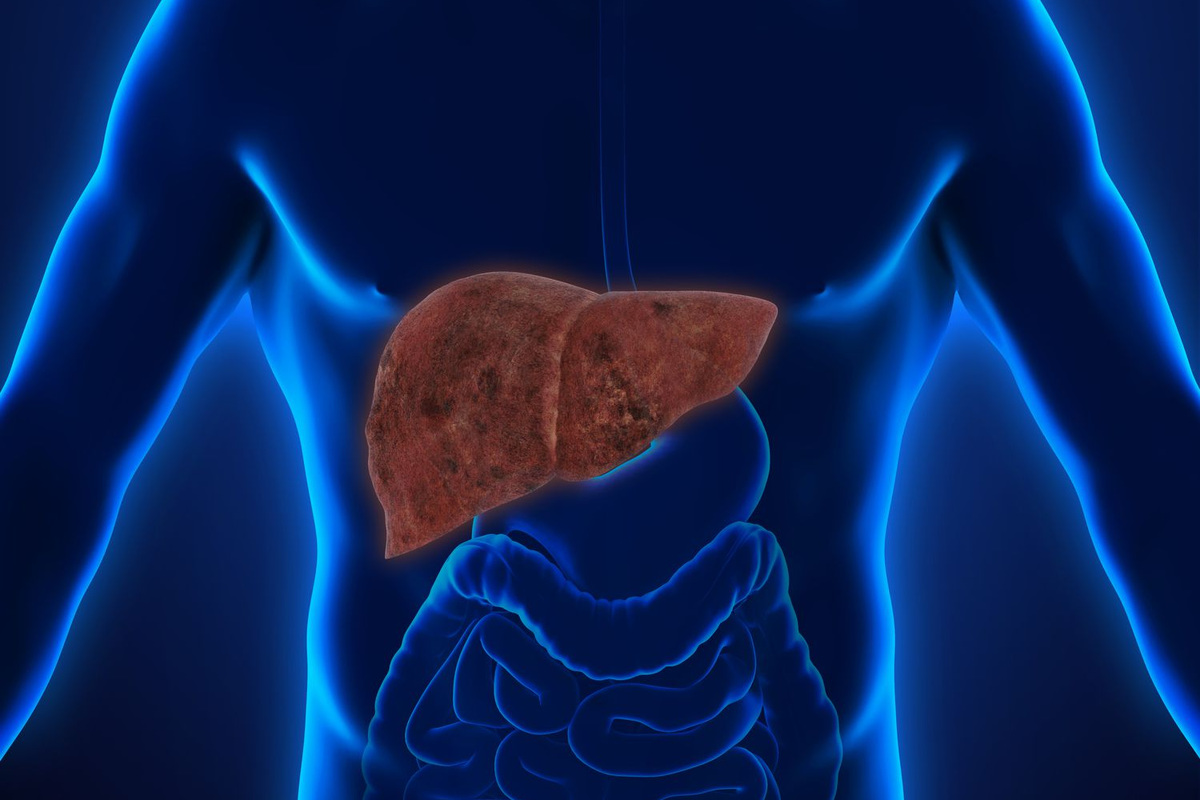

В последние годы в социальных сетях и блогах все чаще встречается необычное явление, известное как “Печень фото”. Этот термин относится к художественному стилю, при котором фотографии печени человека становятся объектом эстетического восприятия и даже искусства. Такие изображения, часто с высоким разрешением и детальной проработкой текстур, привлекают внимание не только медиков и исследователей, но и широкой публики, вызывая удивление и восхищение своей красотой и уникальностью.

Печень фото